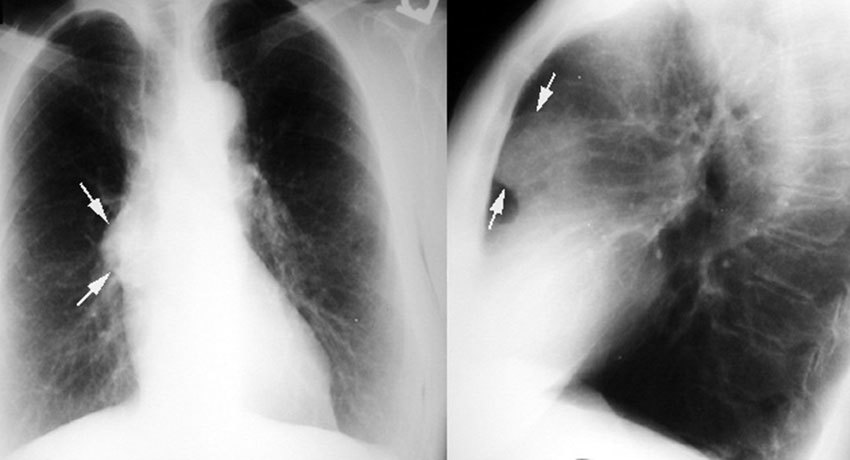

Тимомегалия: что это такое и как проявляется

Раздел: Фотоальбом решений